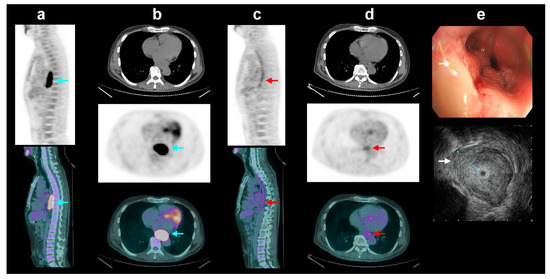

Figure 2. In the group of patients with esophageal squamous cell carcinoma who received neoadjuvant chemoradiotherapy (CRT[+]sub group), a 52-year-old man had intense FDG avidity (blue arrows, SUVmax = 9.6) in the locally advanced esophageal cancer on initial sagittal (a) and transaxial (b) positron emission tomography/computed tomography (PET/CT) images (CT, PET, and fused PET/CT, top to bottom). After neoadjuvant chemoradiotherapy (CRT), the PET/CT images (c,d) showed complete metabolic response without definite residual tumor uptake (red arrows, yfT0). However, post-CRT endoscopic ultrasound (EUS) (e) showed an ulcerative tumor with annular wall thickening and destroyed layer structure (white arrows, maximum tumor thickness = 11.4 mm, yuT3). By coordinating FDG PET/CT and EUS, the complementary T-stage classification was revised to non-T0, making it compatible with post-surgical histopathology results.